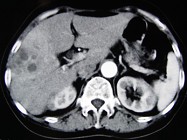

- 单项选择题女,66岁, 右上腹痛,发热伴有黄疸两月余, 消瘦、纳差,影像检查如图, 最可能的诊断为( )

A、胆囊癌及原发性肝癌

B、肝内胆管细胞癌

C、胆囊结石及脂肪肝

D、胆囊结石及肝血管瘤

E、胆囊癌肝转移